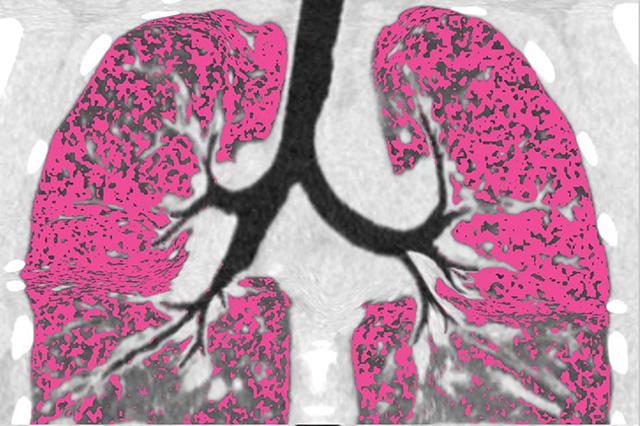

Before the study participants were started on modulators, the researchers went into patients’ lungs with thin cameras called bronchoscopes. They sampled regions that differed in the amount of damage, infection and inflammation. They then revisited the same lung areas a year after treatment to see where infection remained and what lung characteristics were linked to persistent infection.

“A leading idea in the field is that patients remain infected because highly damaged lung regions can’t clear the infection, similar to how damaged tissues in wounds get infected,” said UW Medicine pulmonologist Dr. Sid Kapnadak, who led lung sampling for the study. “If a similar process is responsible for persistent CF lung infections, research can focus on these areas.”

Durfey continued: “However, people who remained infected had infection and inflammation everywhere we looked, including lung areas with very little damage.”